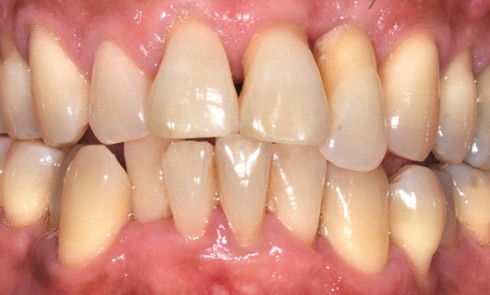

Article réservé à nos abonnés Parodontite sévère : quand l’orthodontie et les traitements biomimétiques redonnent le sourire

Les maladies parodontales entraînent des destructions irréversibles des tissus muqueux et osseux, qui peuvent avoir d’importantes répercussions esthétiques et altérer...